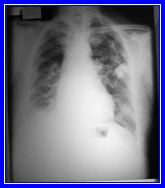

Masculino de 84 años de edad, sin antecedentes heredo-familiares

de importancia, tabaquismo por 15 años durante su juventud

con un índice tabáquico de 9 paquetes/año.

Antecedente laboral de perforista en una mina de oro y plata

por 23 años sin uso de equipo de protección

personal. Inicia su padecimiento hace 20 años caracterizado

por tos con expectoración escasa de predominio matutino

que ha evolucionado con disnea progresiva hasta los medianos

esfuerzos; además refiere hiporexia, astenia y adinamia.

A la exploración física eutérmico, sin

datos de cianosis, campos pulmonares hipoventilados con estertores

crepitantes escasos.

Observe cuidadosamente la placa y de acuerdo a la descripción

del caso opine:

a) Cáncer broncogénico

b) Neumonía basal derecha

c) Derrame pleural

d) Neumoconiosis

e) Bronquitis crónica